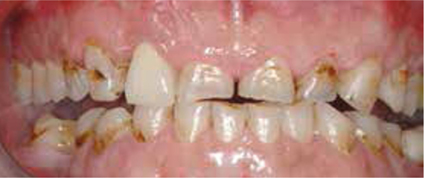

Bij het extraoraal onderzoek zie ik een lichte hypertrofie van de m. masseter. Intraoraal tref ik een ernstig versleten dentitie aan waarbij de slijtage niet passend bij de leeftijd kan worden genoemd (afbeelding 2-7 en tabel 1) .

Afb. 2

Frontaal aanzicht van de dentitie.